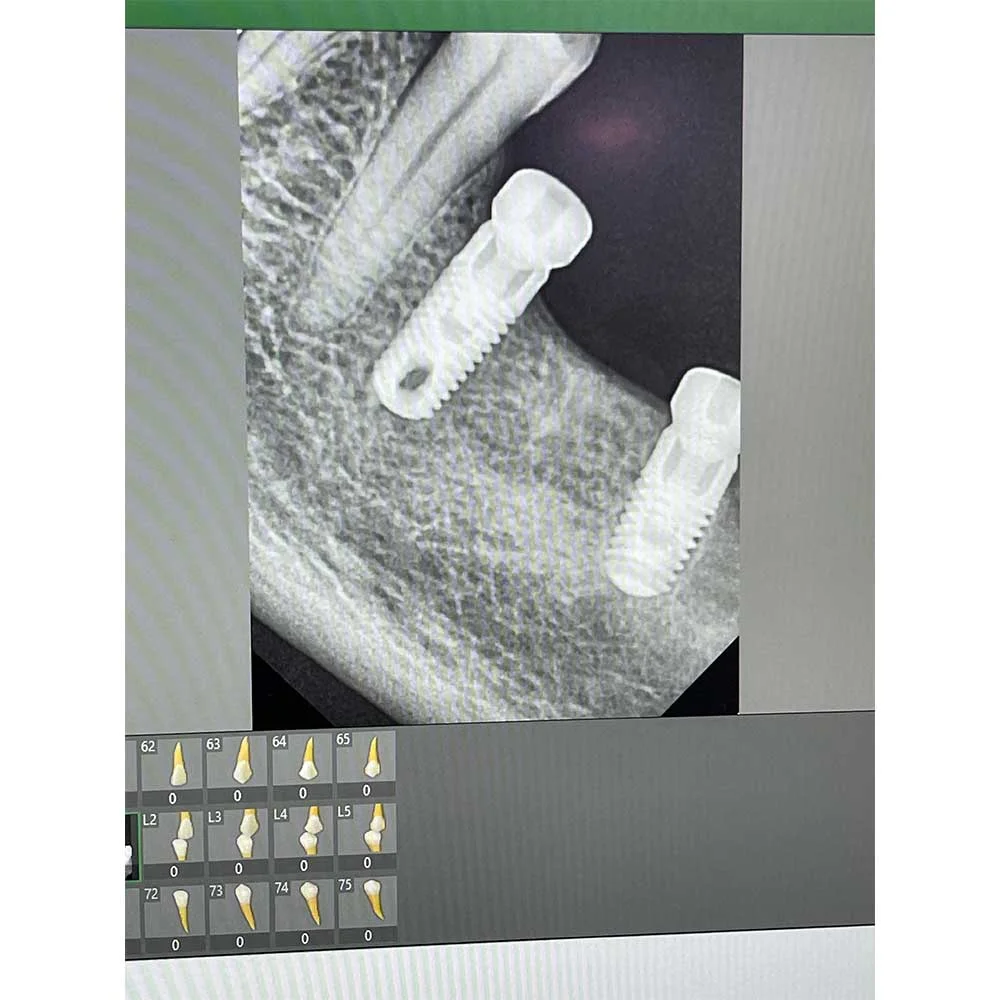

Dental implants are frames made of titanium and fitted into the Jawbone to fill the gap where the teeth were missing. Implants, unlike dentures, are similar to normal teeth, offering a secure base against which crowns, bridges, or full-arch restorations can be built. They not only prevent bone loss but also enable you to maintain your facial shape and enjoy your favourite food without pain.

2. High Technology: We utilise the best equipment to ensure accurate diagnostics and treatment.

Full Mouth Implants

Dental Implants